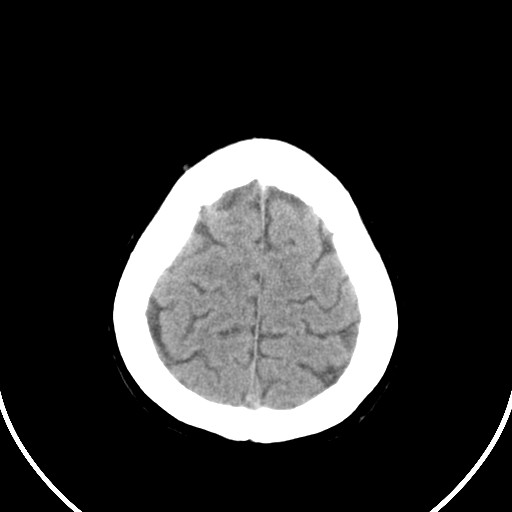

标题: CT21850:女,56岁,右中指淤肿,右手麻痹1天

女,56岁,右中指淤肿,右手麻痹1天

右侧侧脑室旁脑白质腔隙性脑梗死。

右侧基底节多发小梗塞

作者: huangyinshan    时间: 2009-8-25 15:37

右基底结区腔梗

右侧基底节区腔隙性脑梗塞

右侧基底节多发腔梗!

双侧侧脑室额角旁对称性略低密度影,边缘模糊,无占位效应,考虑轻度脑白质稀疏症(病人有高血压吗).,右枕叶低密度影多为伪影,不放心薄扫一下.

考虑脑白质病。

考虑脑白质病

右枕叶条状低密度影不应该忽略可能极具意义